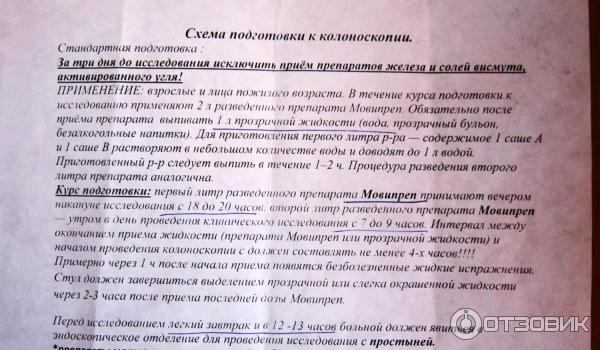

Подготовка к ирригоскопии: необходимые препараты